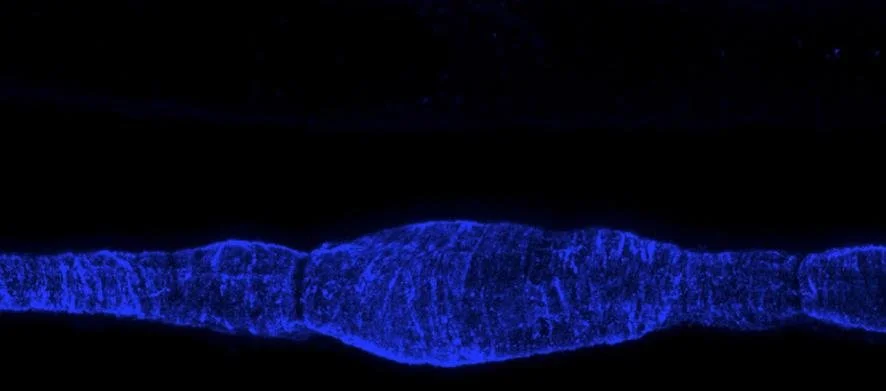

Lymphatic muscle cells in the wall of a rat mesenteric lymphatic vessel. The bulge at the centre of the image indicates the location of a lymphatic valve. From Zawieja et al., Am J Physiol Heart Circ Physiol 302:H643-H653, 2012.

Contraction of lymphatic muscle cells is crucial for propelling lymph through the body. These cells are a hybrid of cardiac, smooth and skeletal muscle types. Experimental evidence on whole cannulated vessels shows that the acto-myosin complex in these individual cells facilitates phasic contractions which in produce most of the pumping action. The smooth muscle components regulate the diameter, and thus the resistance to flow from adjacent vessels. The contractile signature of lymphatics has not been studied at the single-cell level. We aim to induce active contractions in single isolated human lymphatic muscle cells via a custom-built bioreactor and subsequently measure their biomechanics on a substrate through traction force microscopy.